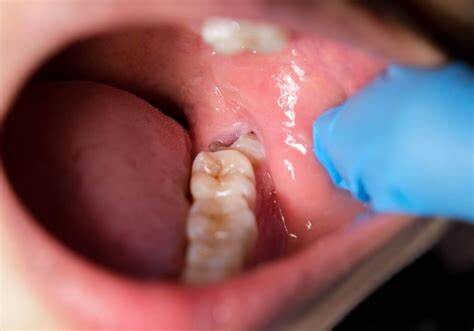

Wisdom teeth promotes Gum Disease

It is a challenging task to clean the area in which the third molars have erupted. Therefore they are at a greater risk of acquiring the periodontal problems. The gum diseases are usually caused by bacteria, and when a tooth can’t be precisely cleaned on a regular basis, the dental plaque gets accumulated around the tooth, which may lead to further complications.